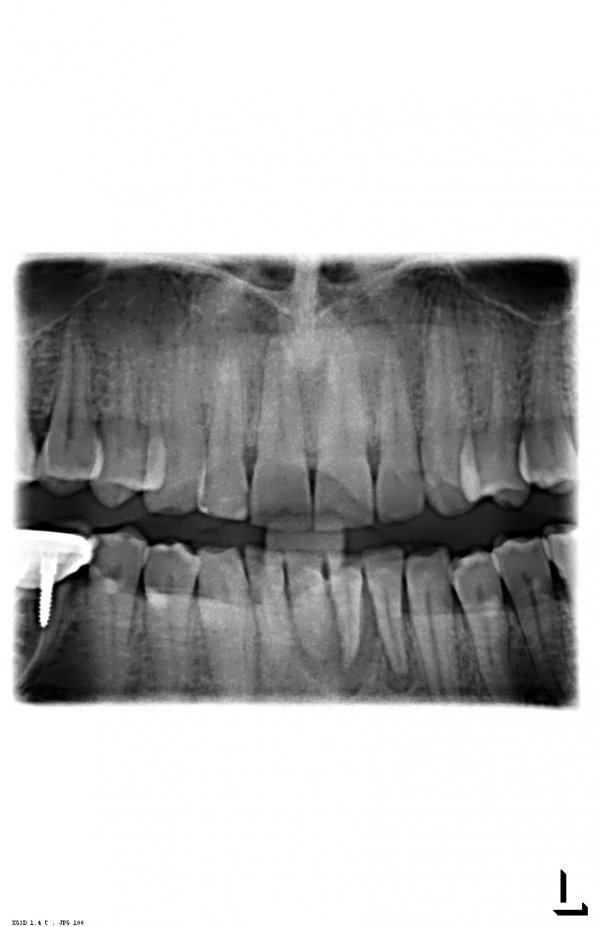

Добрый день. Особых проблем я не вижу, уважаемый пациент. 4.7 зуб необходимо тщательно осмотреть на предмет пригодных тканей для последующего восстановления вкладкой и коронкой, на 4.6 также есть воспаление на верхушке корня, все также необходимо пролечить затем изготовить культевую вкладку и коронку, 3.6 необходимо перелечить, плохая некачественная пломбировка, а также большая по площади пломба, при неблагоприятном исходе может привести к сколу стенки, что в последствии также к потере зуба, 2.6 скорее всего удалится, но еще раз стоит сделать ревизию, 1.6 необходимо перелечить.